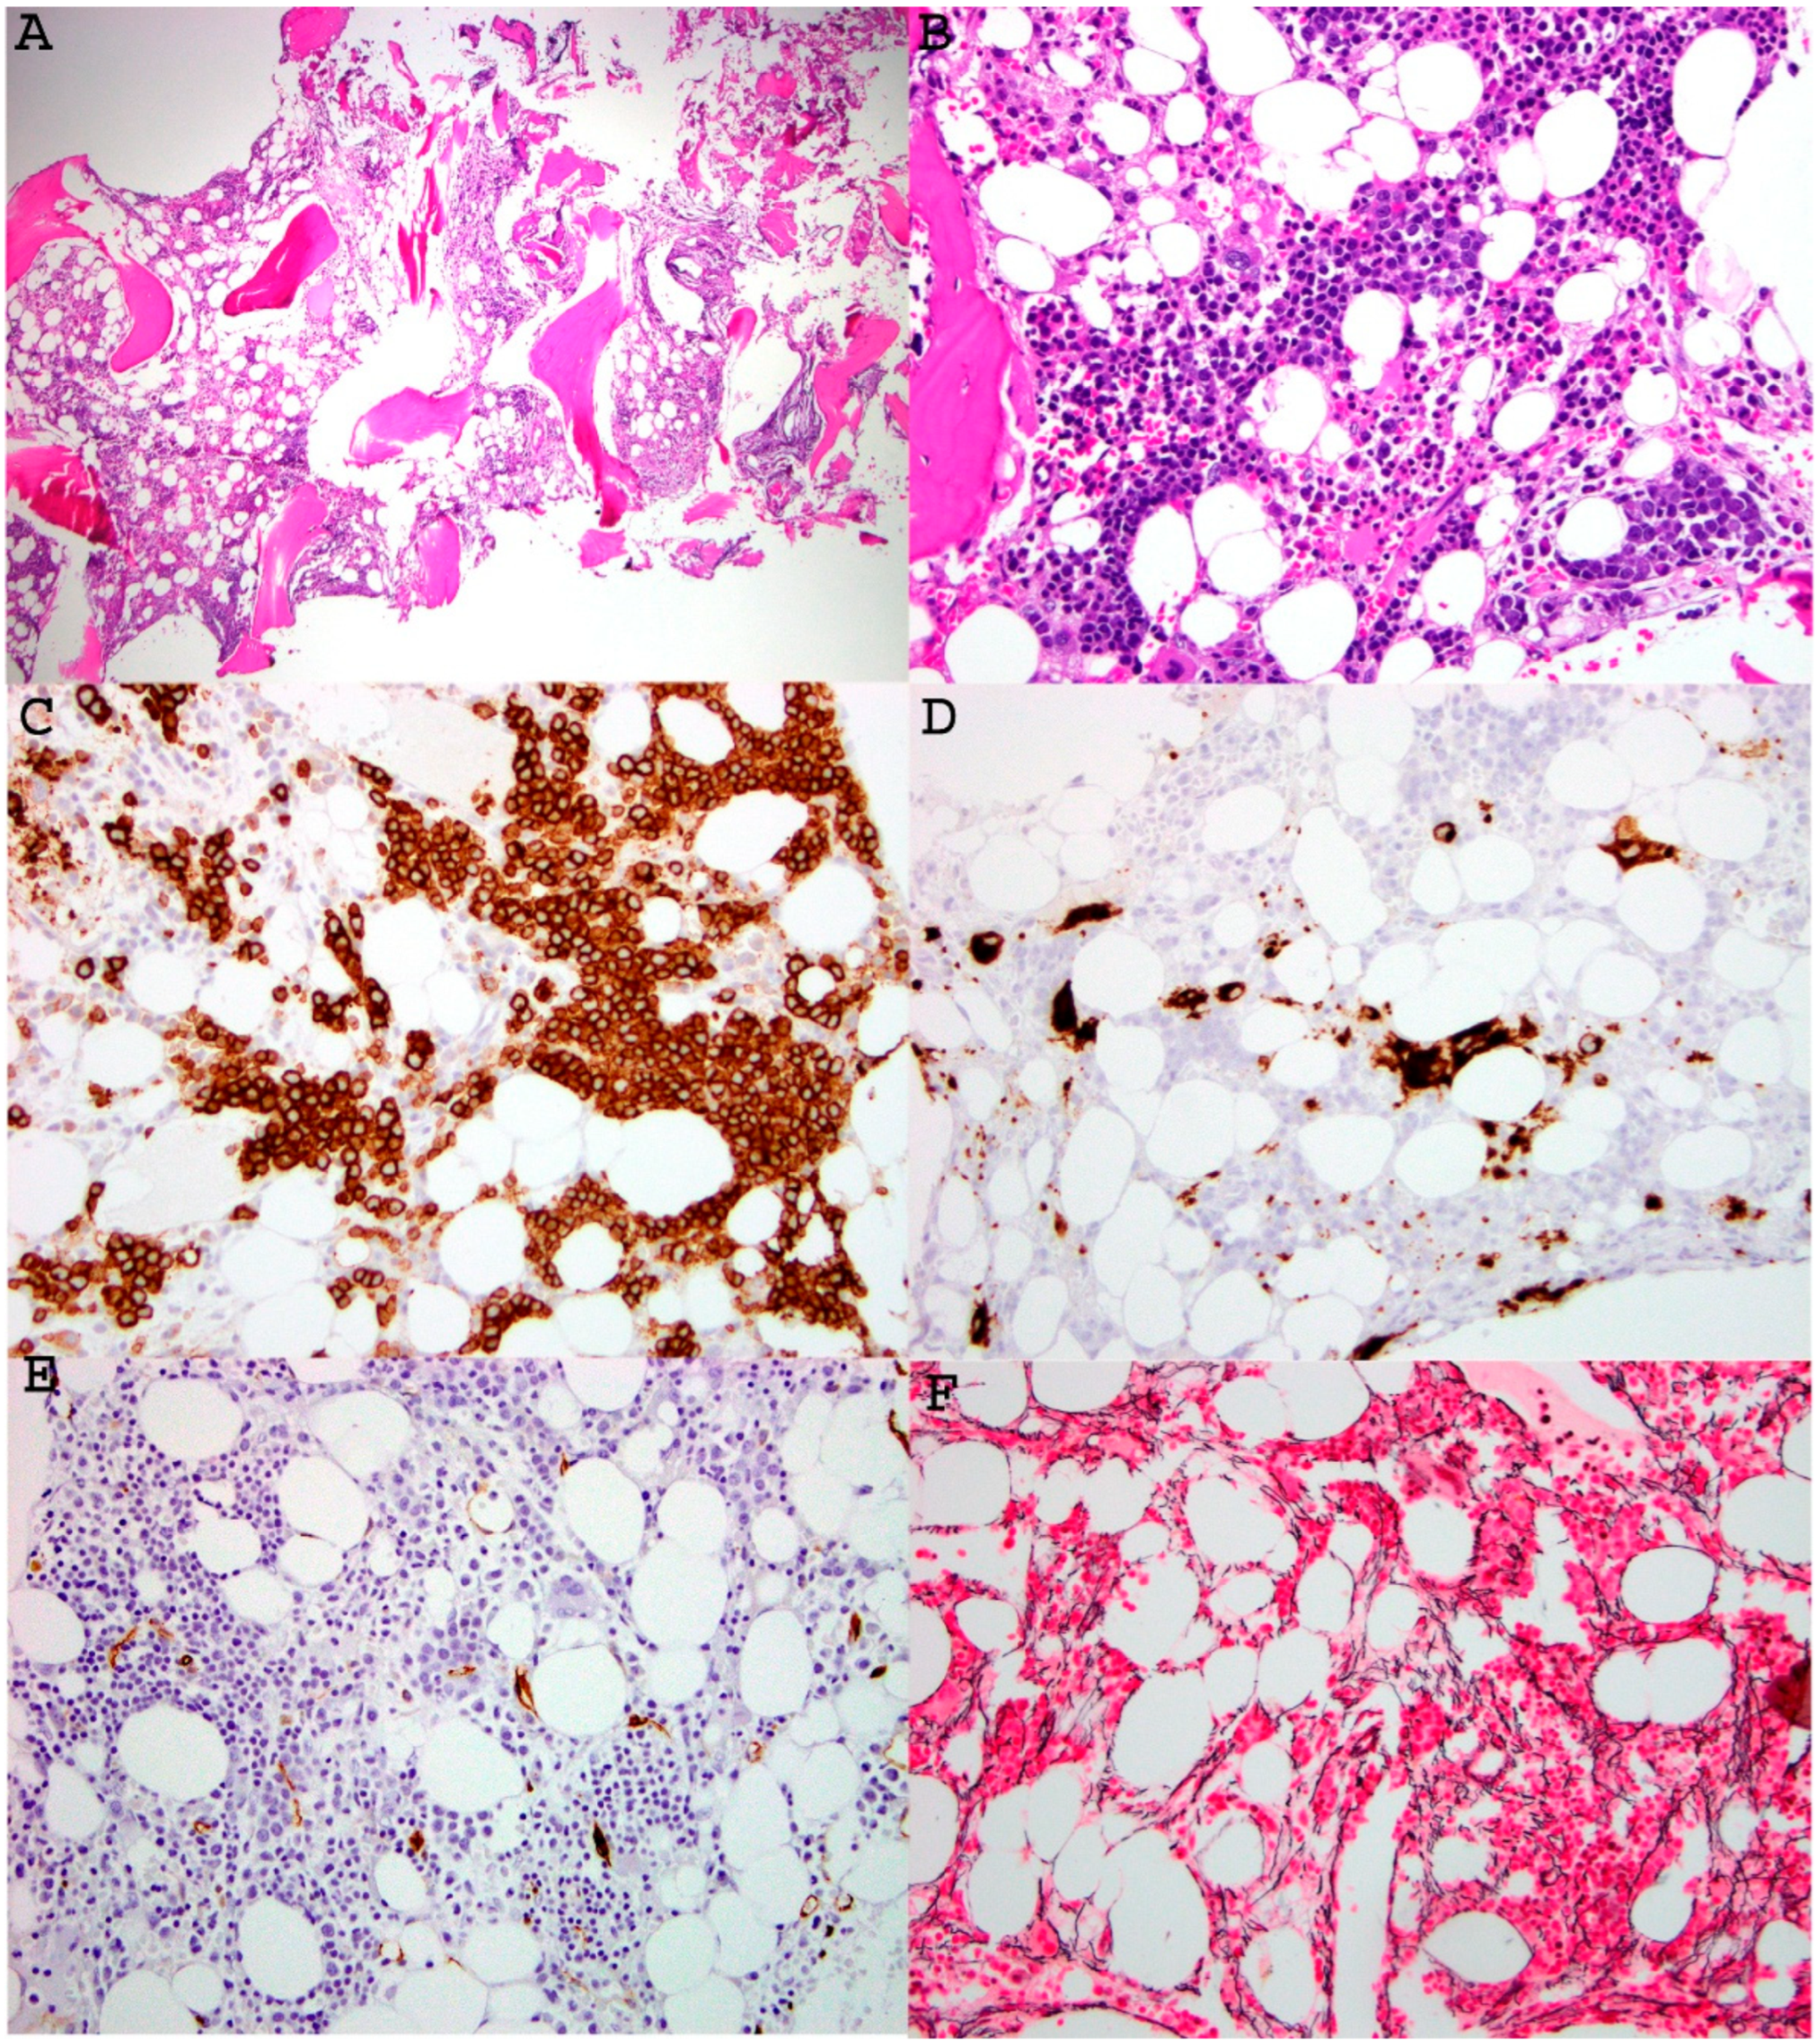

Figure 2. Representative images of bone marrow findings in a 21-year-old patient with MDS associated with germline GATA2 mutation. A low-power view of the bone marrow core biopsy ((A), H&E, ×100) showed patchy fibrosis, decreased myelopoiesis, and atypical/dysplastic megakaryocytes. A medium power of view of the core ((B), H&E, ×200) highlighted erythroid preponderance and left-shifted maturation, and hypolobated megakaryocytes. Myeloid precursors were decreased without morphologic evidence of excess myeloblasts. Immunohistochemical stains were performed on the core biopsy, which showed increased CD71 positive erythroid lineage, CD61-positive dysplastic small megakaryocytes, and no increase in CD34 positive blasts ((CE), immunoperoxidase, ×200). Reticulin stain highlighted mild reticulin fibrosis (MF1-2/3) ((F), reticulin stain, ×200). NGS study confirmed presence of GATA2: p.L315Cfs*11, c.942-943delinsC (VAF 49.7%) in both bone marrow and skin specimens, supporting a diagnosis of GATA2 germline mutation. This image is provided courtesy of Dr. Ling Zhang.

The GATA2 gene, located on 3q21, is a key transcription factor and plays an essential role in regulation of normal hematopoiesis and lymphangiogenesis. GATA2 mutations impair hematopoiesis, resulting in defective trilineage differentiation and enhancing over-differentiation in monocytes, eventually leading to myeloid malignancies (Figure 2).